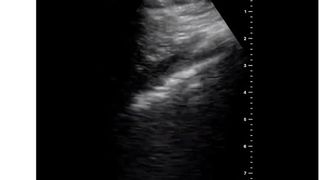

În cea de-a doua zi de autoizolare, medicul a scris: „Ziua 2 după ce am fost diagnosticat cu COVID-19. Durere mai slabă în gât, tuse și durere de cap, fără dificultăți respiratorii sau durere în piept”.